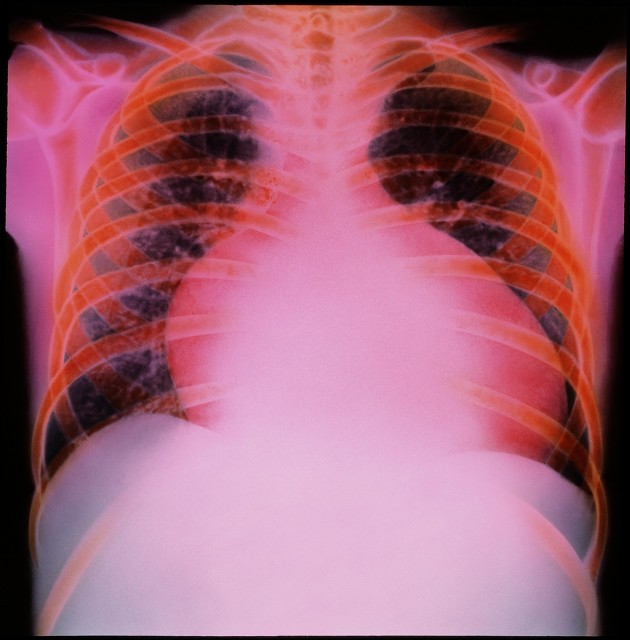

林某槽,男性,74岁,一个反复咳喘十余年的老肺病病人,长期咳嗽,气喘,一到冬天就发作,一喘就是一个月,没完没了,走路都困难,上不了楼梯,走不了一百步,平常血压又低。在家需要辅助吸氧治疗,自备吸氧机,每天吸氧二三次,一次大概吸半小时到一小时,生活质量挺差的。 医院诊断:“慢性阻塞性肺病急性发作,慢性肺源性心脏病,冠状动脉粥样硬化性心脏病,心绞痛,心功能3级。”

这次因为感冒再次诱发咳嗽,气喘,呼吸困难,不能平卧,下肢水肿来住院。经过检查诊断:“慢性阻塞性肺病急性加重,慢慢肺源性心脏病,冠状动脉粥样硬化性心脏病,心力衰竭”。

因此期待他能够给病人带来良好疗效。考虑到病人血压偏低,长期维持在110/70mmHg左右。根据说明书,从小剂量开始试用,并取得很显著效果,一周后病人的射血分数从用前的23%回升到43%,症状也明显改善,血压无明显变化。经过半个月的住院治疗,病人基本摆脱了心衰的困扰。出院后,根据病人血压情况,和心功能改善情况,诺欣妥增加到常规剂量。目前病人能够正常出门散步,体重也明显恢复,食欲改善,进食增加。虽然,病人仍然需要辅助吸氧氧疗,相比没有使用诺欣妥,生活质量明显提高。复查心功能,病人射血分数也恢复到53%左右。